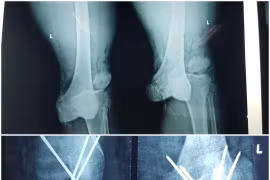

Tỷ lệ tổn thương do chấn thương hàng năm khoảng 3,5/1000 người, vì vậy tổn thương khớp gối là tổn thương hay gặp nhất trong chấn thương. Các tổn thương khớp gối đa dạng và phức tạp cần chú ý chữa trị sớm.

(khoahocdoisong.vn) - Sụn chêm có vai trò quan trọng trong hoạt động chức năng của khớp gối. Sụn chêm lại rất dễ bị tổn thương trong các chấn thương khớp gối và là một trong những nguyên nhân quan trọng gây thoái hóa khớp gối.

(khoahocdoisong.vn) - Tổn thương khớp gối do bệnh lý hoặc chấn thương mà điều trị bảo tồn không kết quả, bệnh nhân đau không đi lại được, mất chức năng khớp gối thường được chỉ định thay khớp gối nhân tạo.